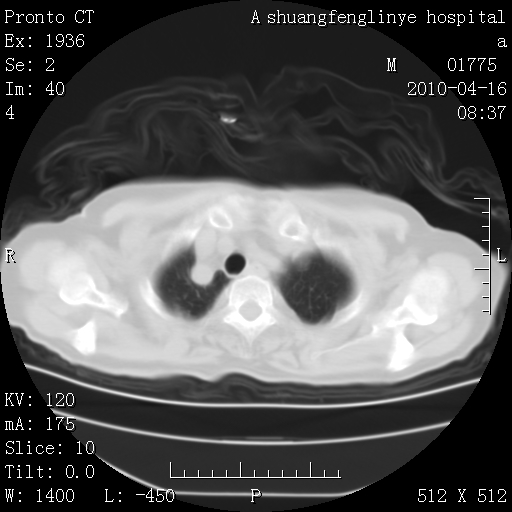

标题: CT25784:咳痰、请会诊!结核?

陈旧性结核,胃腔扩大,脾脏受压后移

考虑左肺上叶增殖灶、纤维灶。

慢支肺气肿,左上陈旧性结核,主动脉冠脉钙化

1)左肺上叶结核(纤维、增殖病灶)。2)冠状动脉及主动脉钙化。

1)左肺上叶结核(纤维、增殖病灶)。2)冠状动脉及主动脉钙化。肺动脉高压